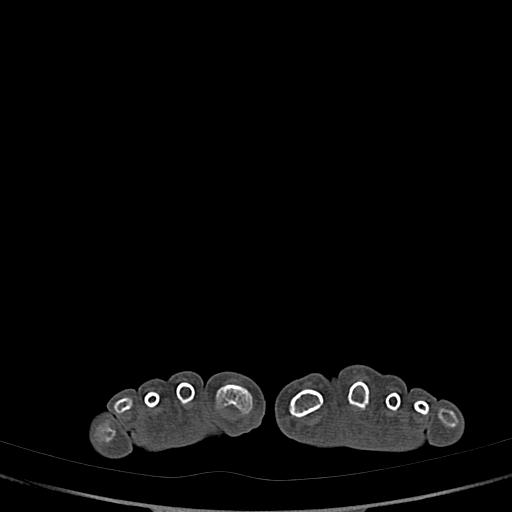

标题: CT13415:M72Y,跖趾关节病变,请会诊 [打印本页]

标题: CT13415:M72Y,跖趾关节病变,请会诊

男72岁左侧跖趾关节肿痛15年,查压痛。

骨软骨瘤可能性大,请上传x光片.

不象软骨瘤,

考虑退行性骨关节病。